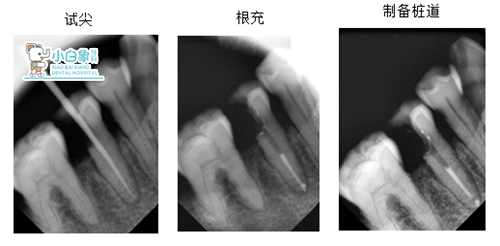

X线:45低密度影近髓角

治疗:45必兰麻醉下去腐,开髓揭顶,预备根管一根,根长19mm,荡洗,隔湿干燥,根充,制备桩道,树脂粘结红色纤维桩,预备全冠,扫像,设计,粘结全冠,调合。